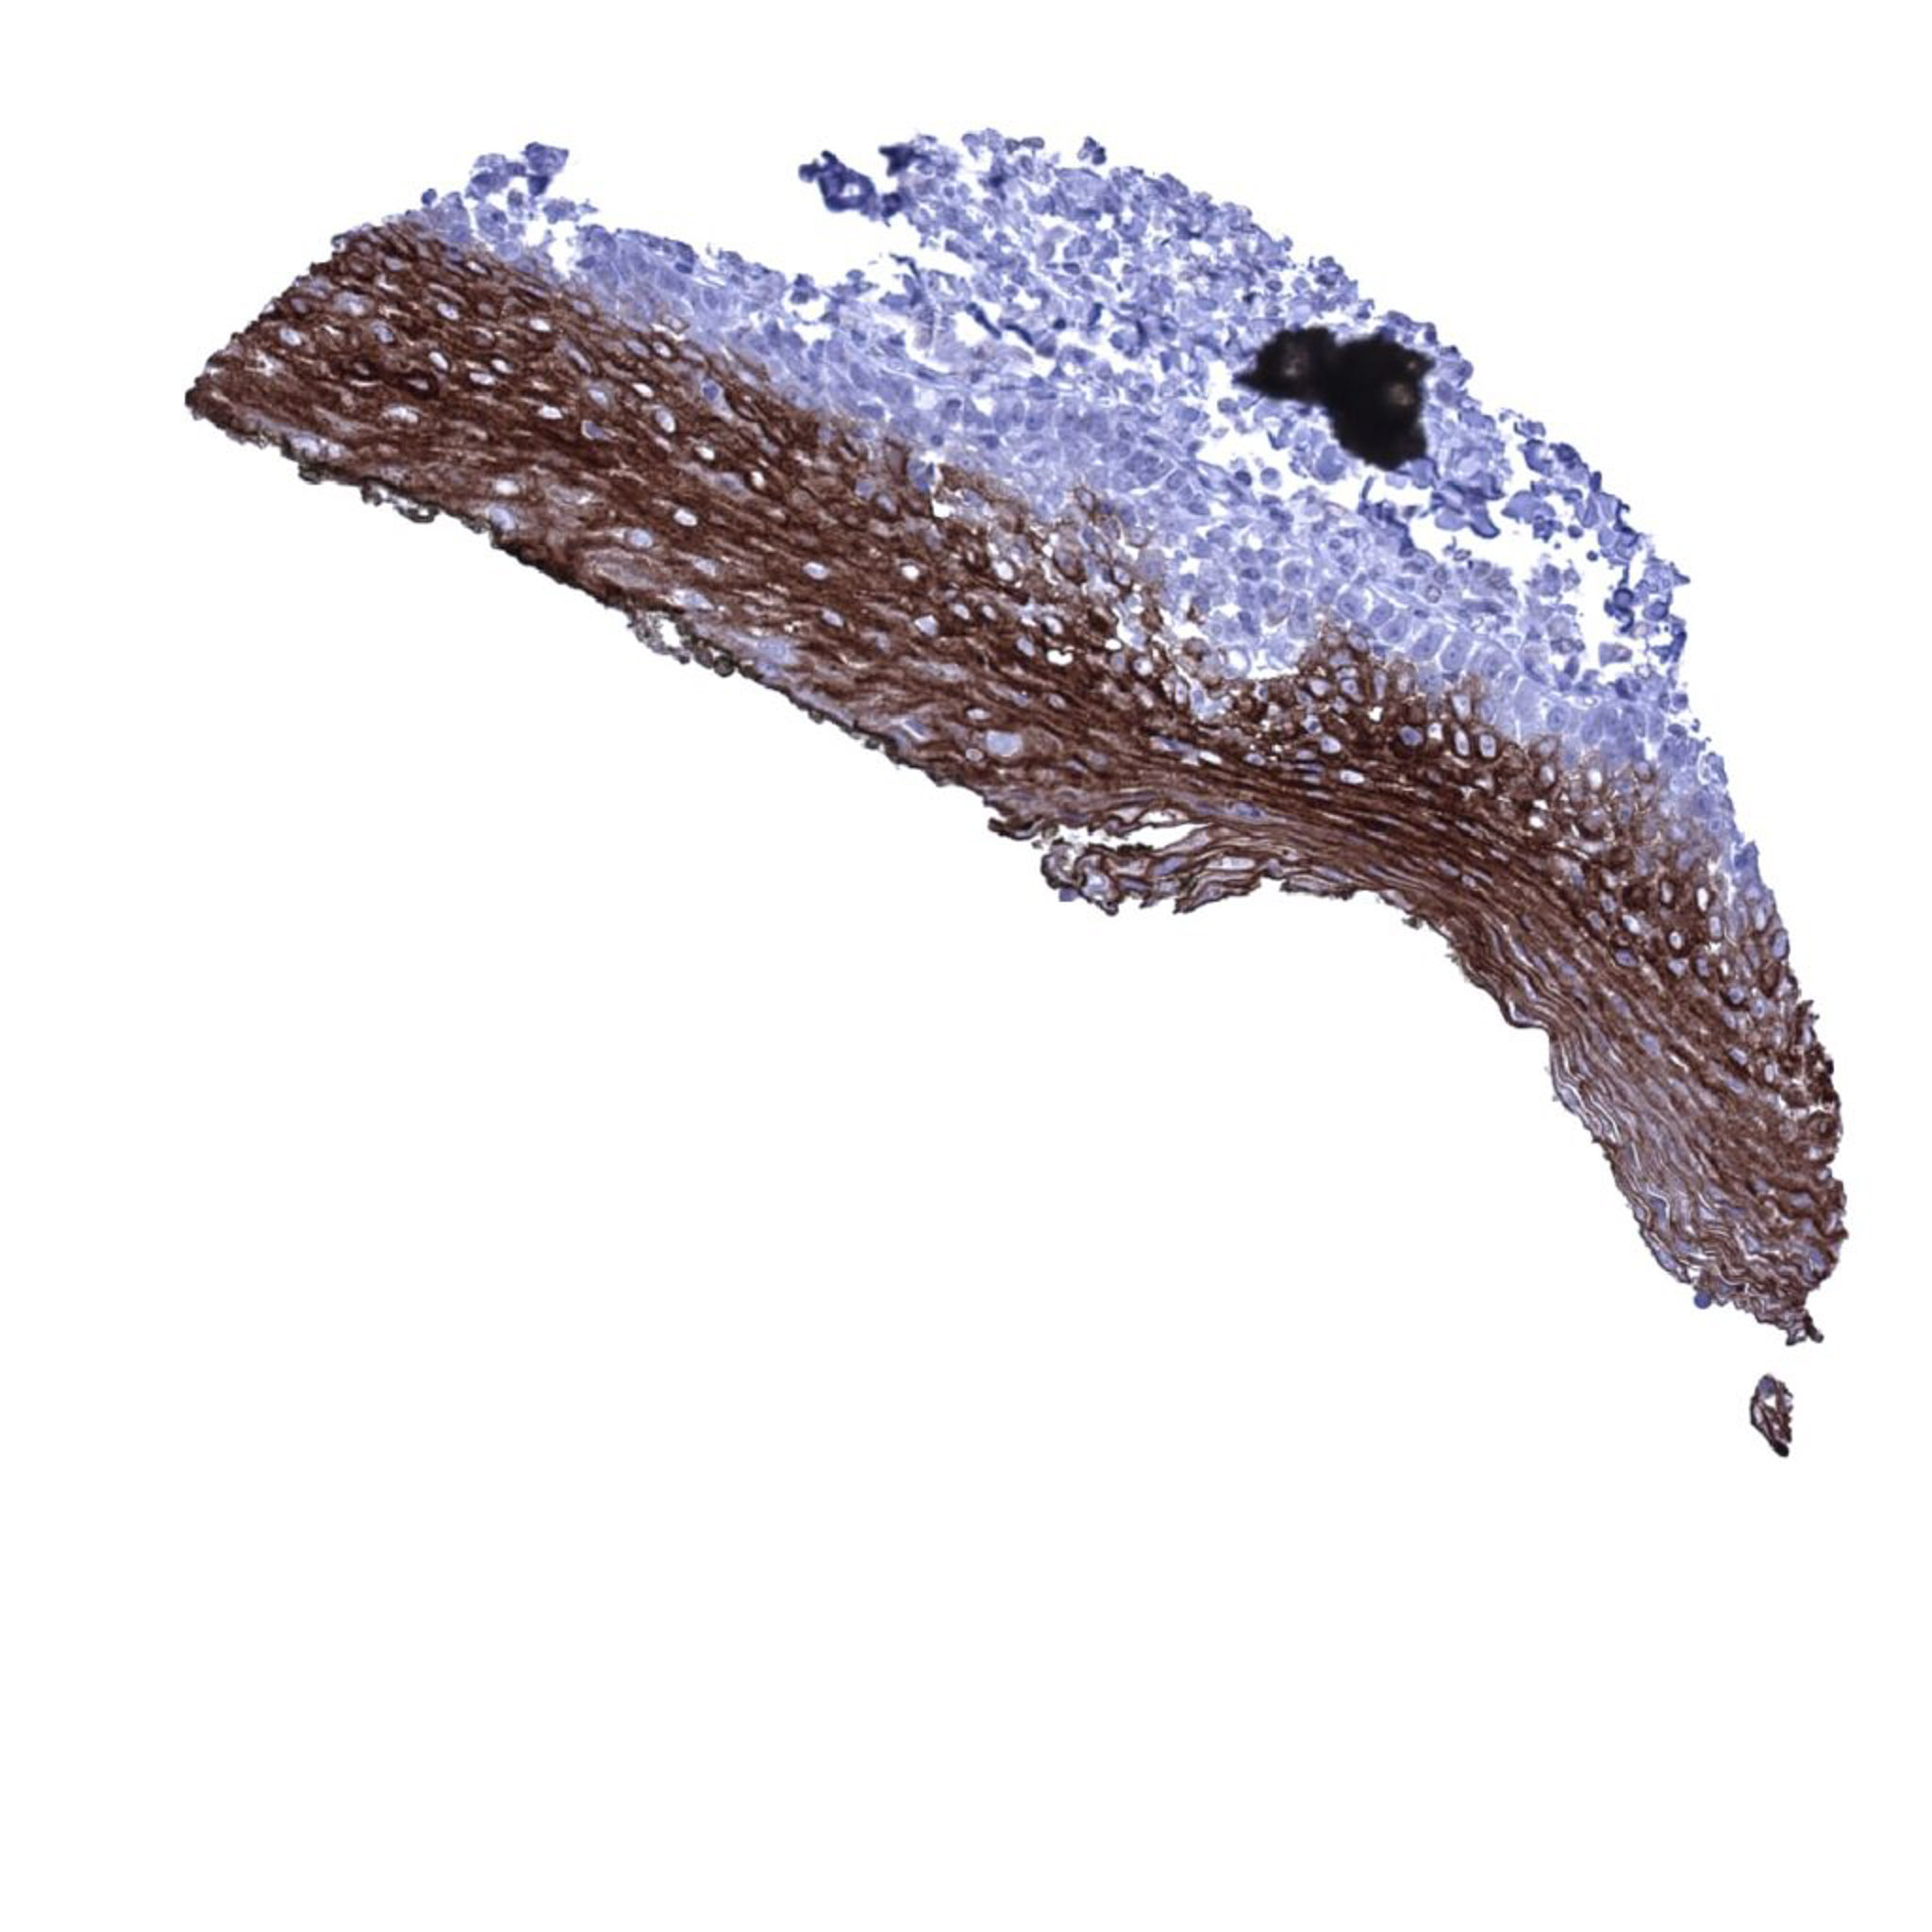

Esophagus, squamous epithelium – Scattered UKP1b positive cells can be seen in the non-keratinizing squamous epithelium of the esophagus